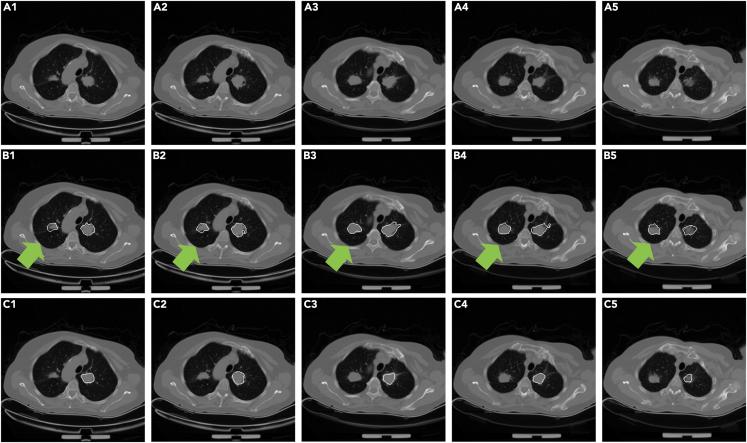

一种用于CT图像中肺炎、肺结节和肺结核自动分割的通用方法。

A general approach for automatic segmentation of pneumonia, pulmonary nodule, and tuberculosis in CT images.

Proposing a general segmentation approach for lung lesions, including pulmonary nodules, pneumonia, and tuberculosis, in CT images will improve efficiency in radiology. However, the performance of generative adversarial networks is hampered by the limited availability of annotated samples and the catastrophic forgetting of the discriminator, whereas the universality of traditional morphology-based methods is insufficient for segmenting diverse lung lesions. A cascaded dual-attention network with a context-aware pyramid feature extraction module was designed to address these challenges. A self-supervised rotation loss was designed to mitigate discriminator forgetting. The proposed model achieved Dice coefficients of 70.92, 73.55, and 68.52% on multi-center pneumonia, lung nodule, and tuberculosis test datasets, respectively. No significant decrease in accuracy was observed (p > 0.10) when a small training sample size was used. The cyclic training of the discriminator was reduced with self-supervised rotation loss (p < 0.01). The proposed approach is promising for segmenting multiple lung lesion types in CT images.

摘要

提出一种针对CT图像中肺部病变(包括肺结节、肺炎和肺结核)的通用分割方法将提高放射学的效率。然而,生成对抗网络的性能受到注释样本可用性有限以及判别器灾难性遗忘的阻碍,而传统的基于形态学的方法的通用性不足以分割各种肺部病变。设计了一种带有上下文感知金字塔特征提取模块的级联双注意力网络来应对这些挑战。设计了一种自监督旋转损失来减轻判别器遗忘。所提出的模型在多中心肺炎、肺结节和肺结核测试数据集上分别实现了70.92%、73.55%和68.52%的骰子系数。当使用小训练样本量时,未观察到准确性有显著下降(p>0.10)。通过自监督旋转损失减少了判别器的循环训练(p<0.01)。所提出的方法在分割CT图像中的多种肺部病变类型方面很有前景。